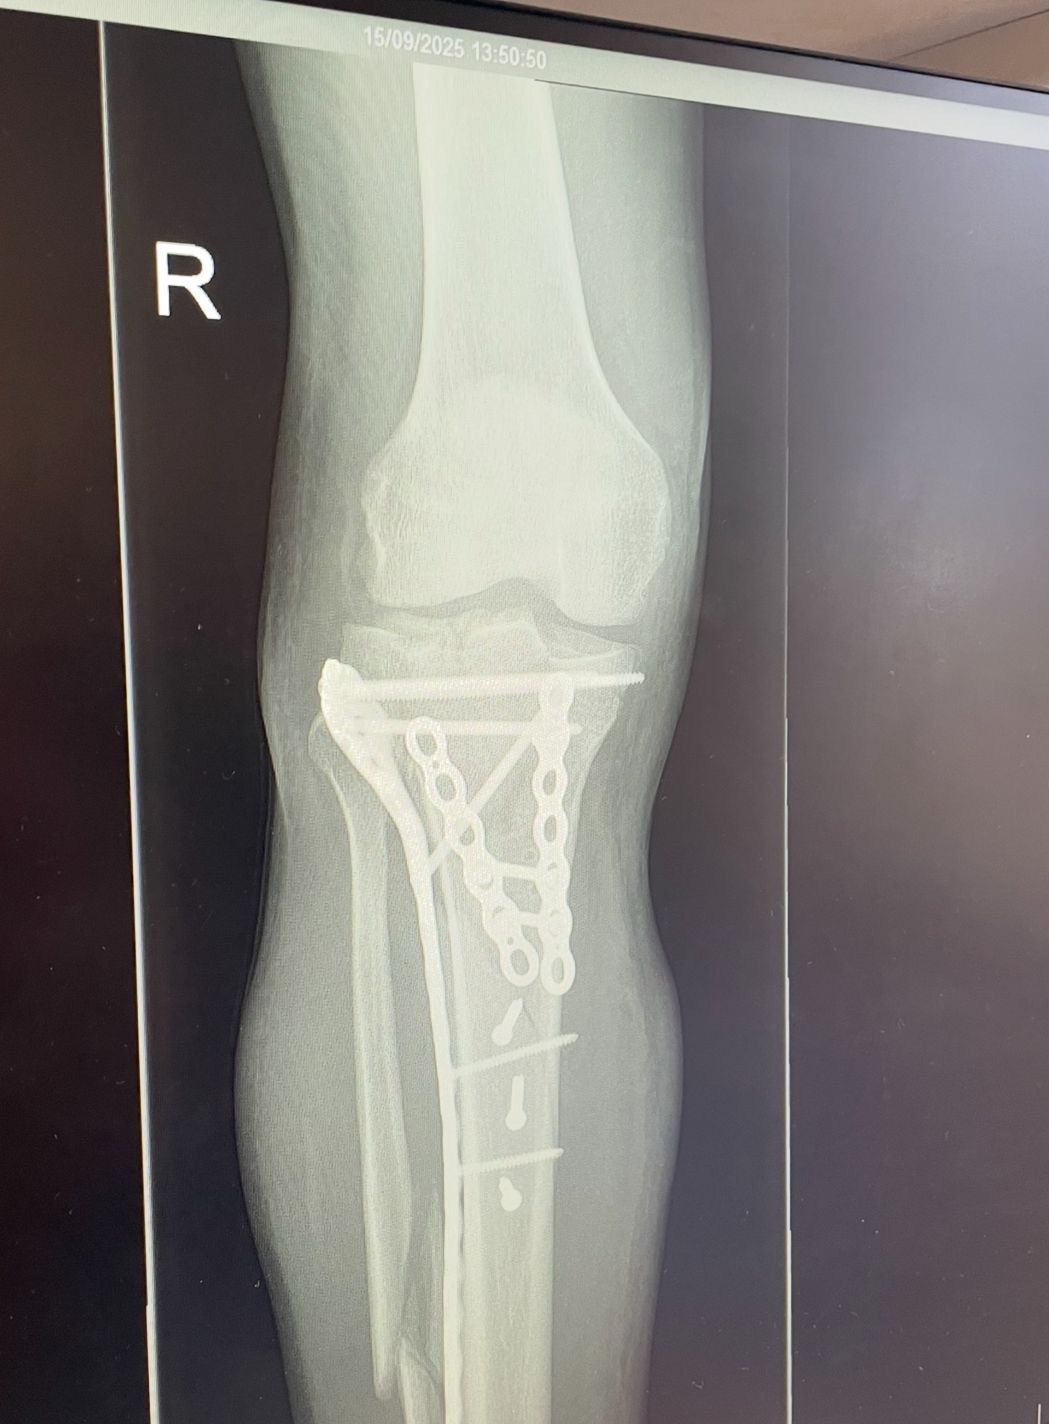

• A tibial plateau fracture

• A tibial spiral fracture

• A broken fibula

• And the tibial plateau break was so severe it nearly severed his main artery

It wasn’t just painful — it was dangerous. He needed metalwork, plates, screws, and a long recovery ahead of him. Physically and mentally, it’s been rough.